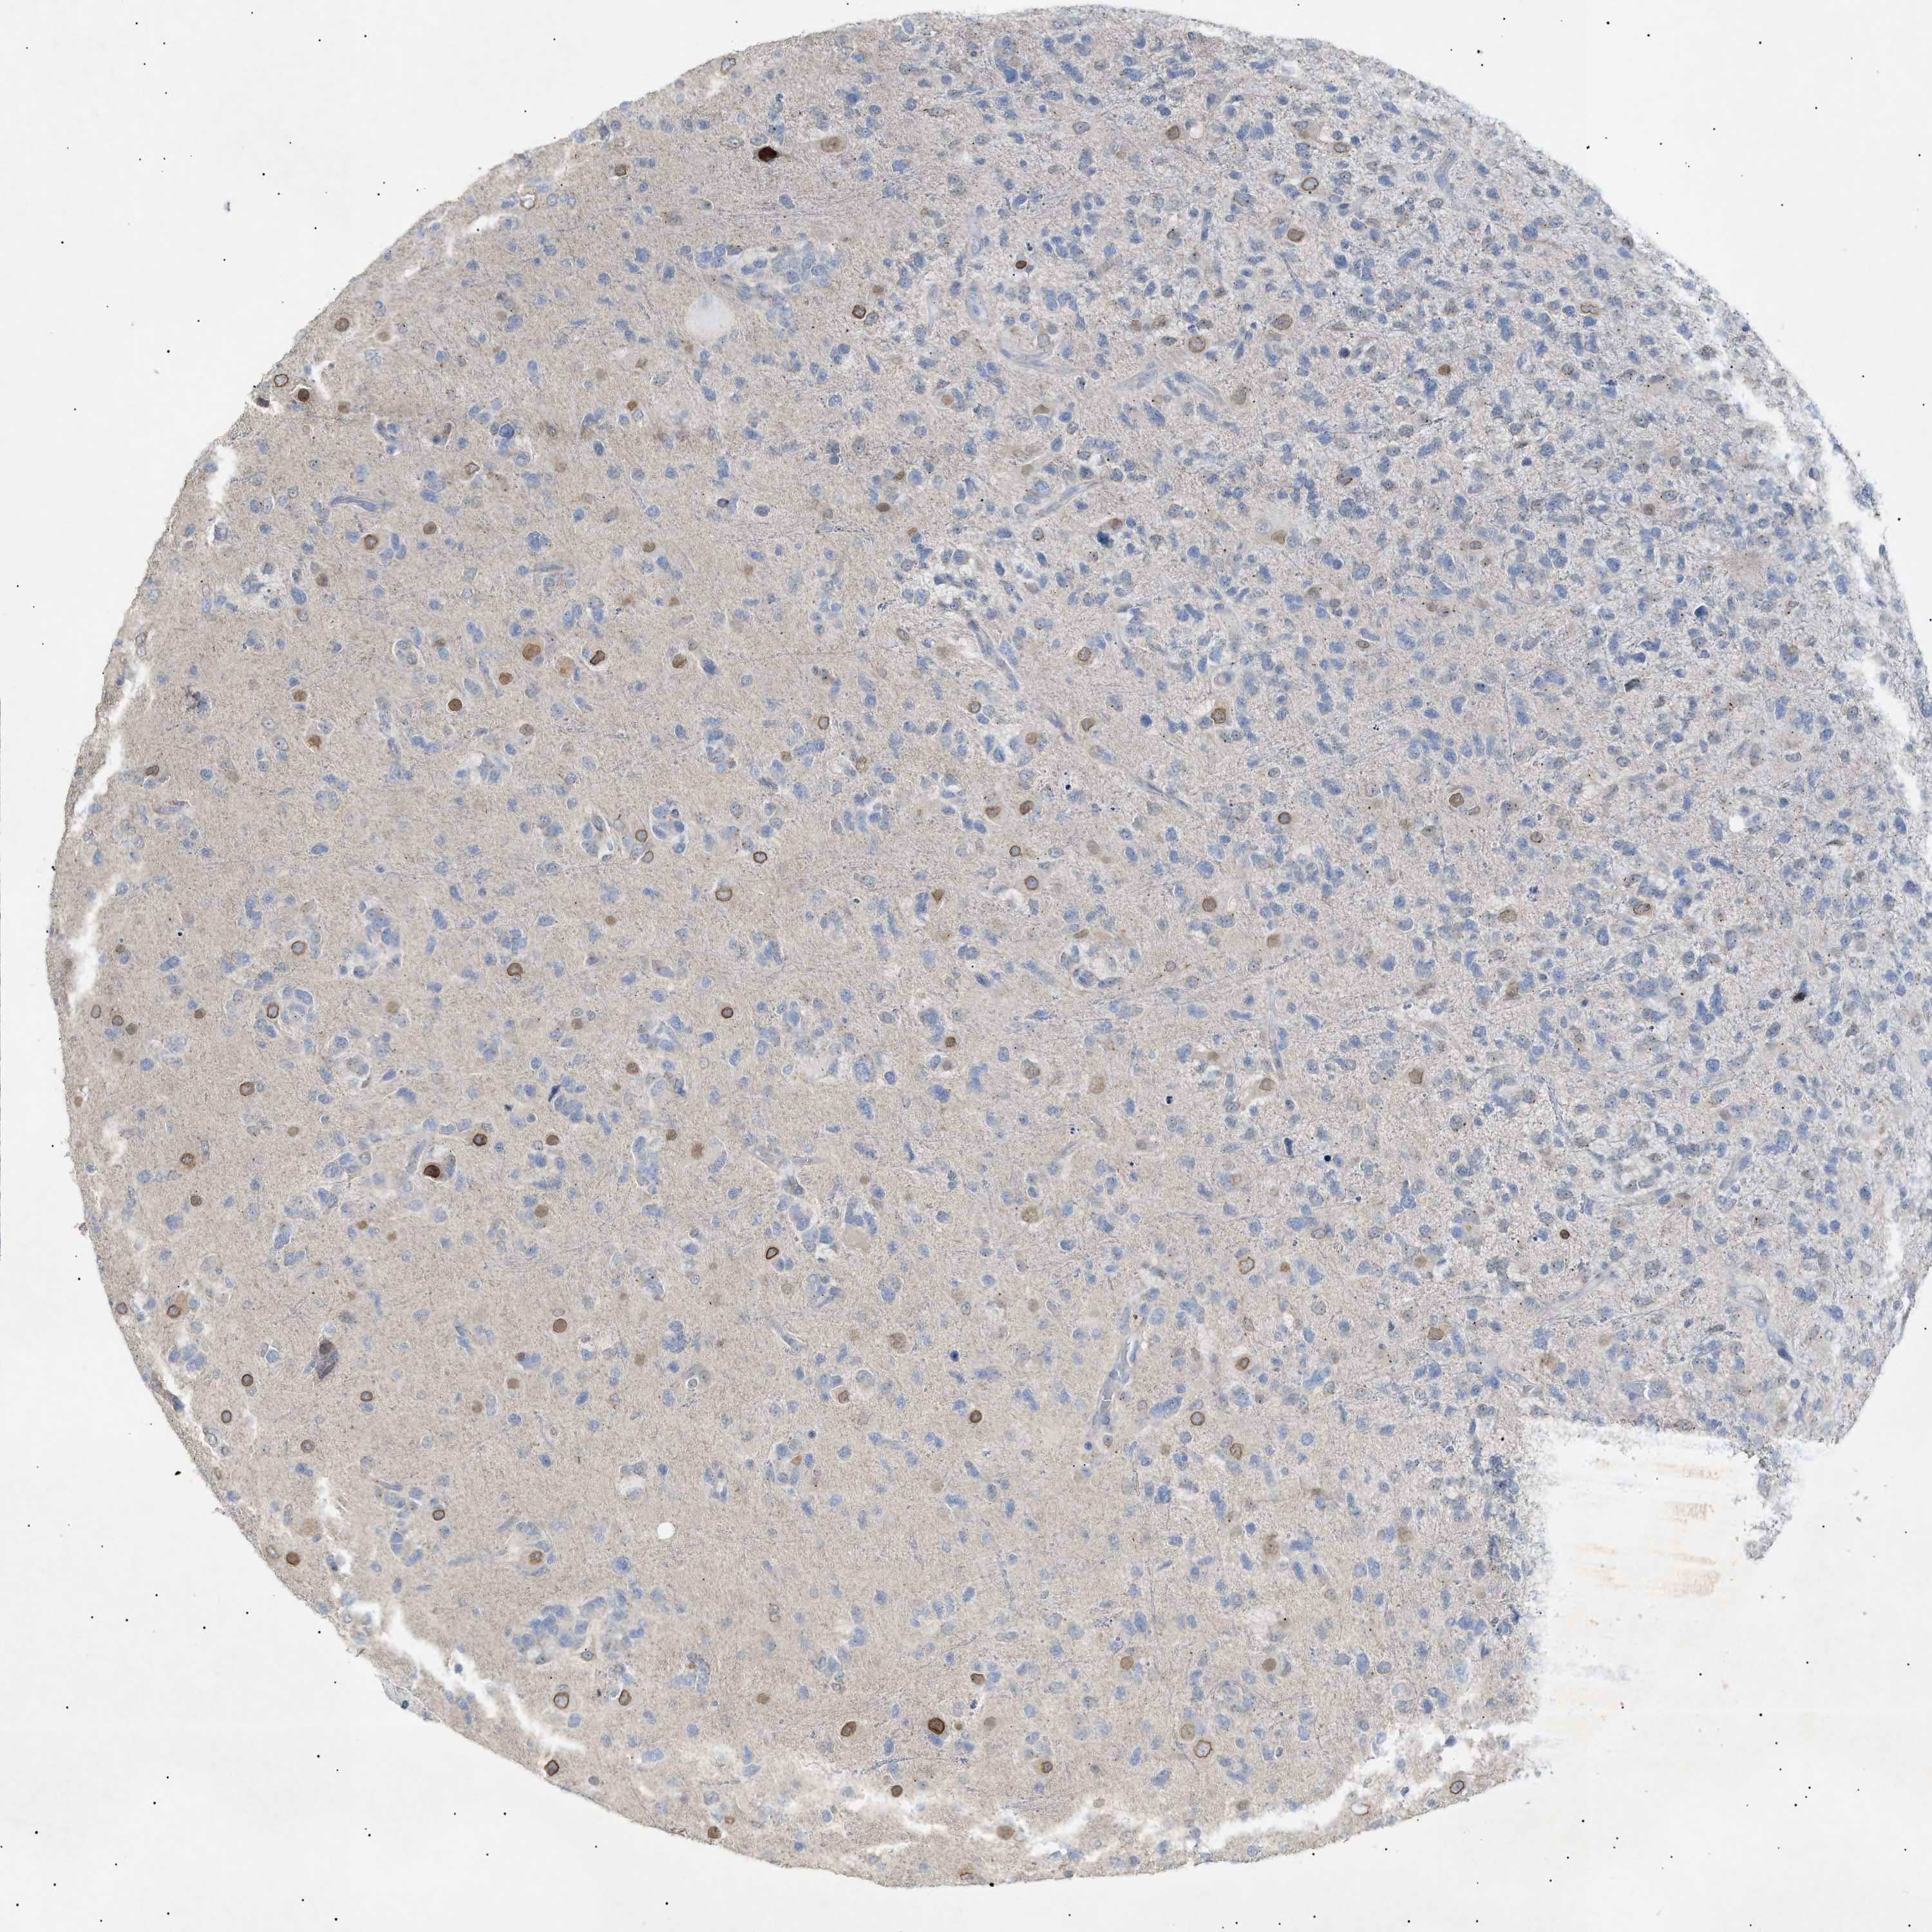

GLIOMA - Protein expressioni

A mouse-over function shows sample information and annotation data. Click on an image to view it in a full screen mode. Samples can be filtered based on level of antibody staining by selecting one or several of the following categories: high, medium, low and not detected. The assay and annotation is described here.

Note that samples used for immunohistochemistry by the Human Protein Atlas do not correspond to samples in the TCGA dataset.

Antibody stainingi

Antibody staining in the annotated cell types in the current human tissue is reported as not detected, low, medium, or high, based on conventional immunohistochemistry profiling in selected tissues. This score is based on the combination of the staining intensity and fraction of stained cells.

Each image is clickable and will lead to virtual microscopy that enables deeper exploration of all samples and also displays staining intensity scores, fraction scores and subcellular localization as well as patient and tissue information for each sample.

Antibody HPA015064

Antibody HPA071684

Glioma, malignant, High grade

Glioma, malignant, Low grade